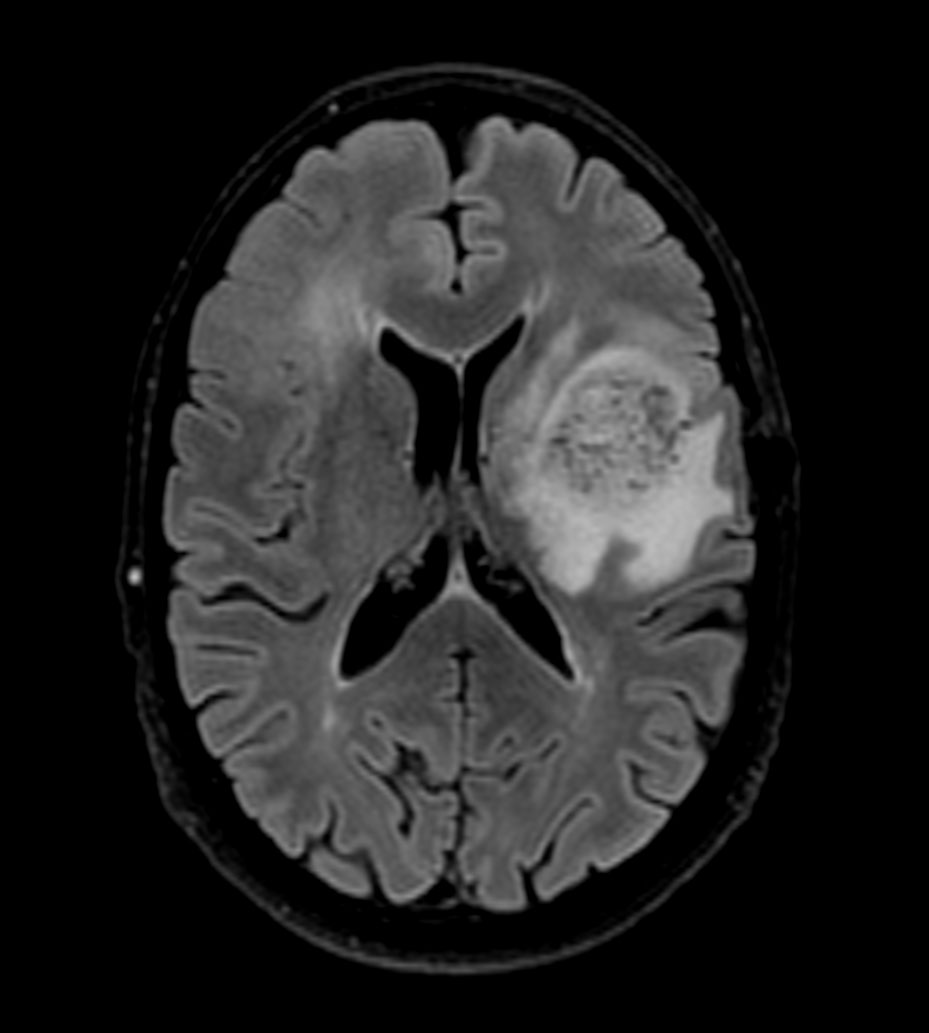

3D BrainVIEW FLAIR (axial reformat)